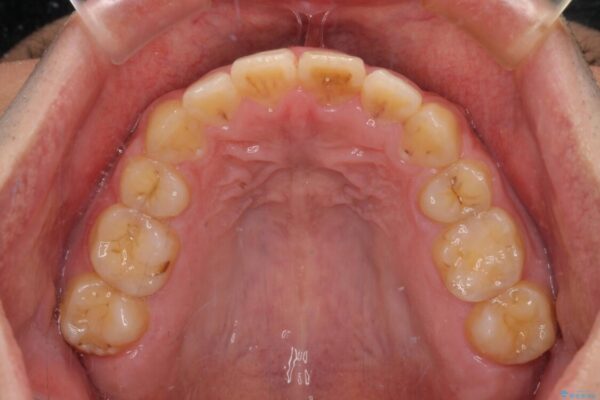

治療後

• 後戻りでデコボコの前歯 インビザライン矯正治療 治療後画像

治療後について

下顎骨が左側に変位しているため、正中が合わないことは予想できましたが、歯列が整った後も咬み合わせが安定せず、咬み合わせを落ち着かせるために1年以上の期間を要しました。

噛みにくさの改善に時間がかかってしまうことがインビザラインの欠点の1つといえます。